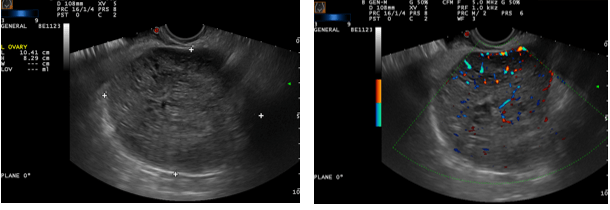

These photos taken during a transvaginal ultrasound show a solid mass in the left ovary about the size of a grapefruit. The right photo adds color Doppler to the examination and shows that the mass is full of blood vessels. These findings are, unfortunately, most often found in an ovarian malignancy. This mass proved to be a granulosa cell tumor in this young lady.